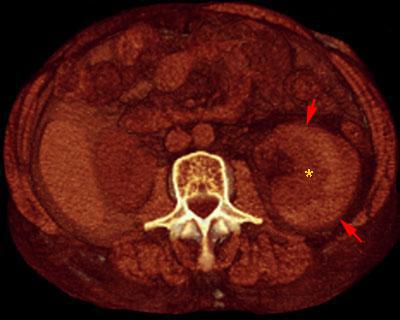

Hematoma subcapsular